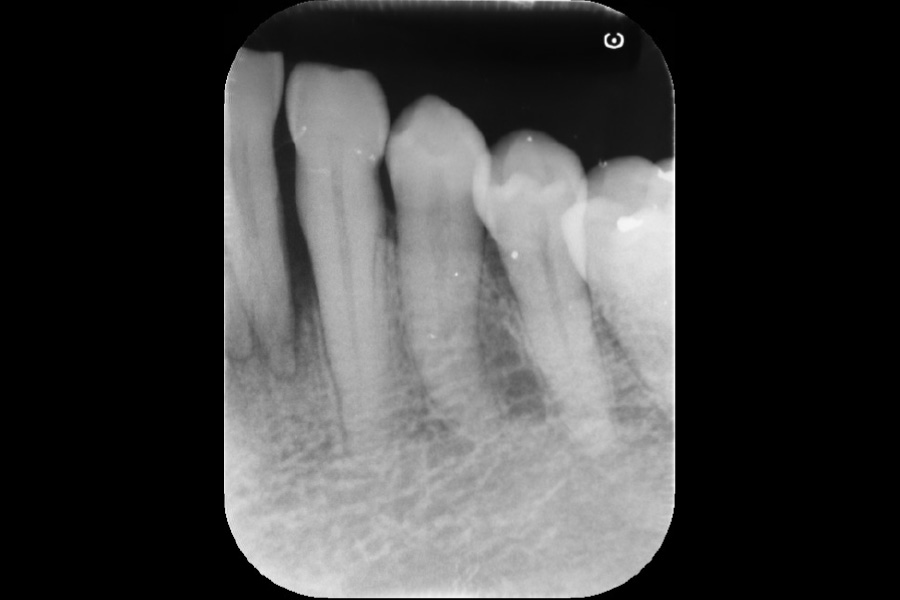

下の前歯から出血する

【歯周組織再生療法】

- 主訴

- 下の前歯から出血する

- 治療内容

- 左下2遠心に垂直性骨吸収が認められたためエムドゲインと骨補填材を用いて歯周組織再生療法を行った

- 治療に伴うリスク

- 歯肉退縮、知覚過敏